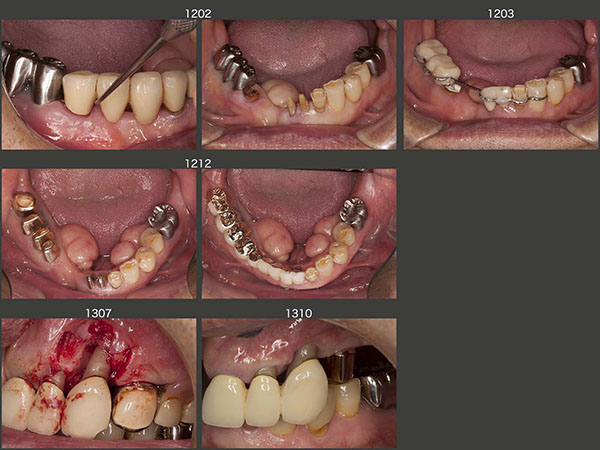

6.コーヌス義歯、術後対応でインプラントを使用

2003年12月初診の58歳女性.本格的な治療開始は,左下4の歯根破折による痛みが生じた06年3月から.まず,左下4を抜去し,当初はスライド下段に示すようなパーシャルデンチャーを8月に装着した.しかし,咬合面の金属色,左下3のクラスプの審美障害等から受け入れられず,結局インプラントを2本植立した.(06年9月オペ,07年5月補綴装置装着,スライド右下は07年11月,インプラント上部構造の咬合面は金属にして頂いた.)